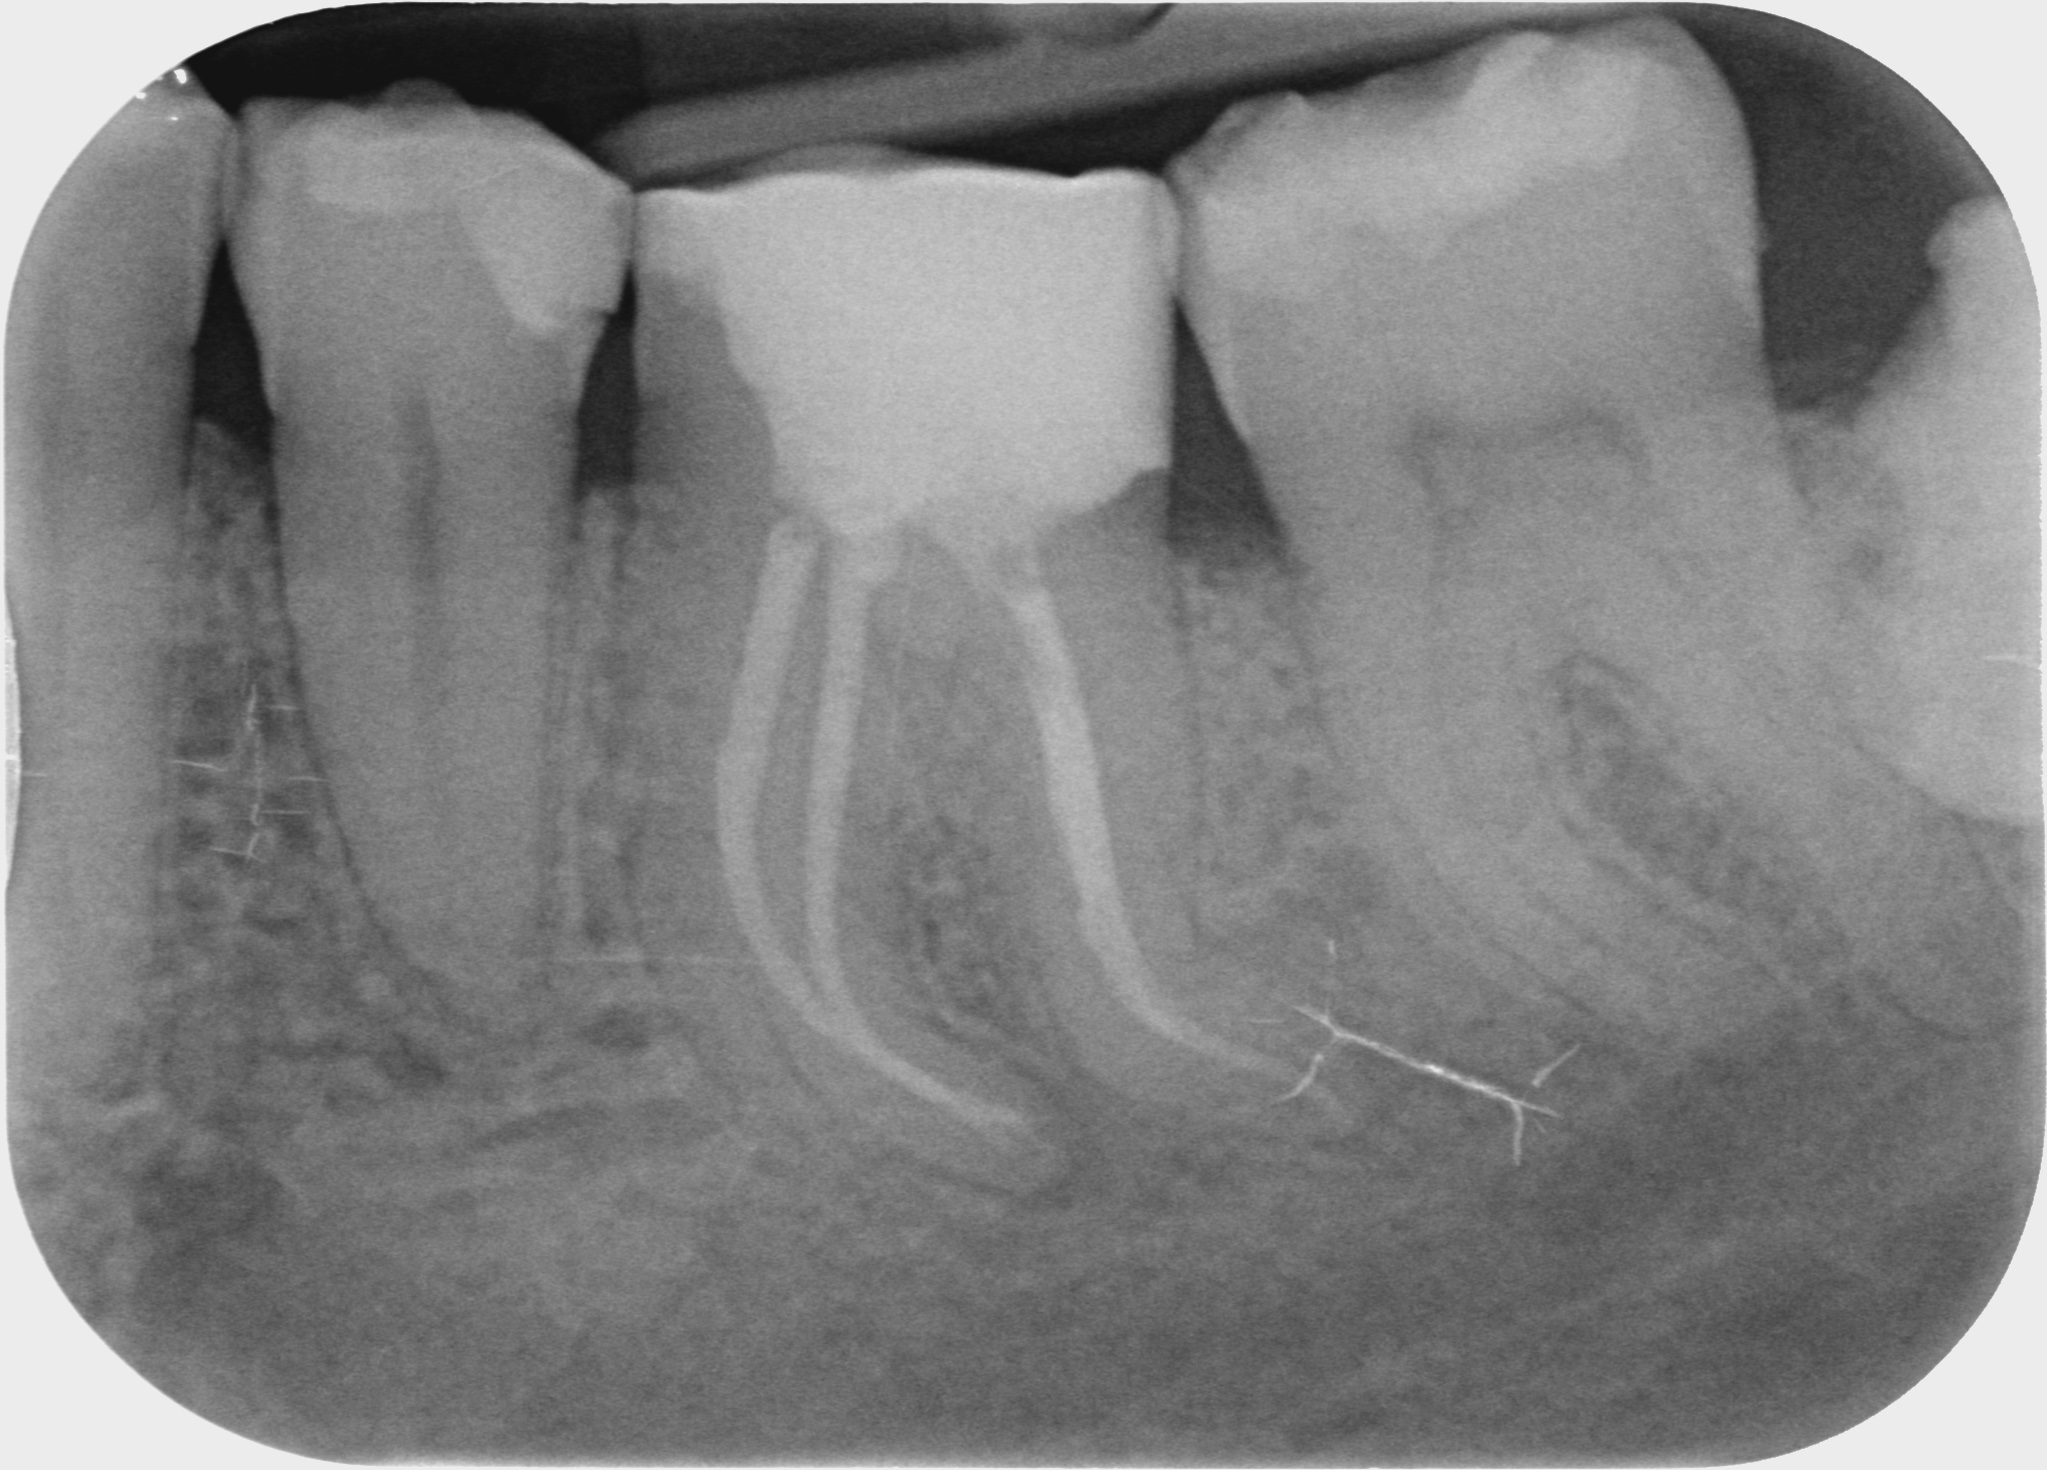

Fallbeispiele

Zum Vergrössern klicken